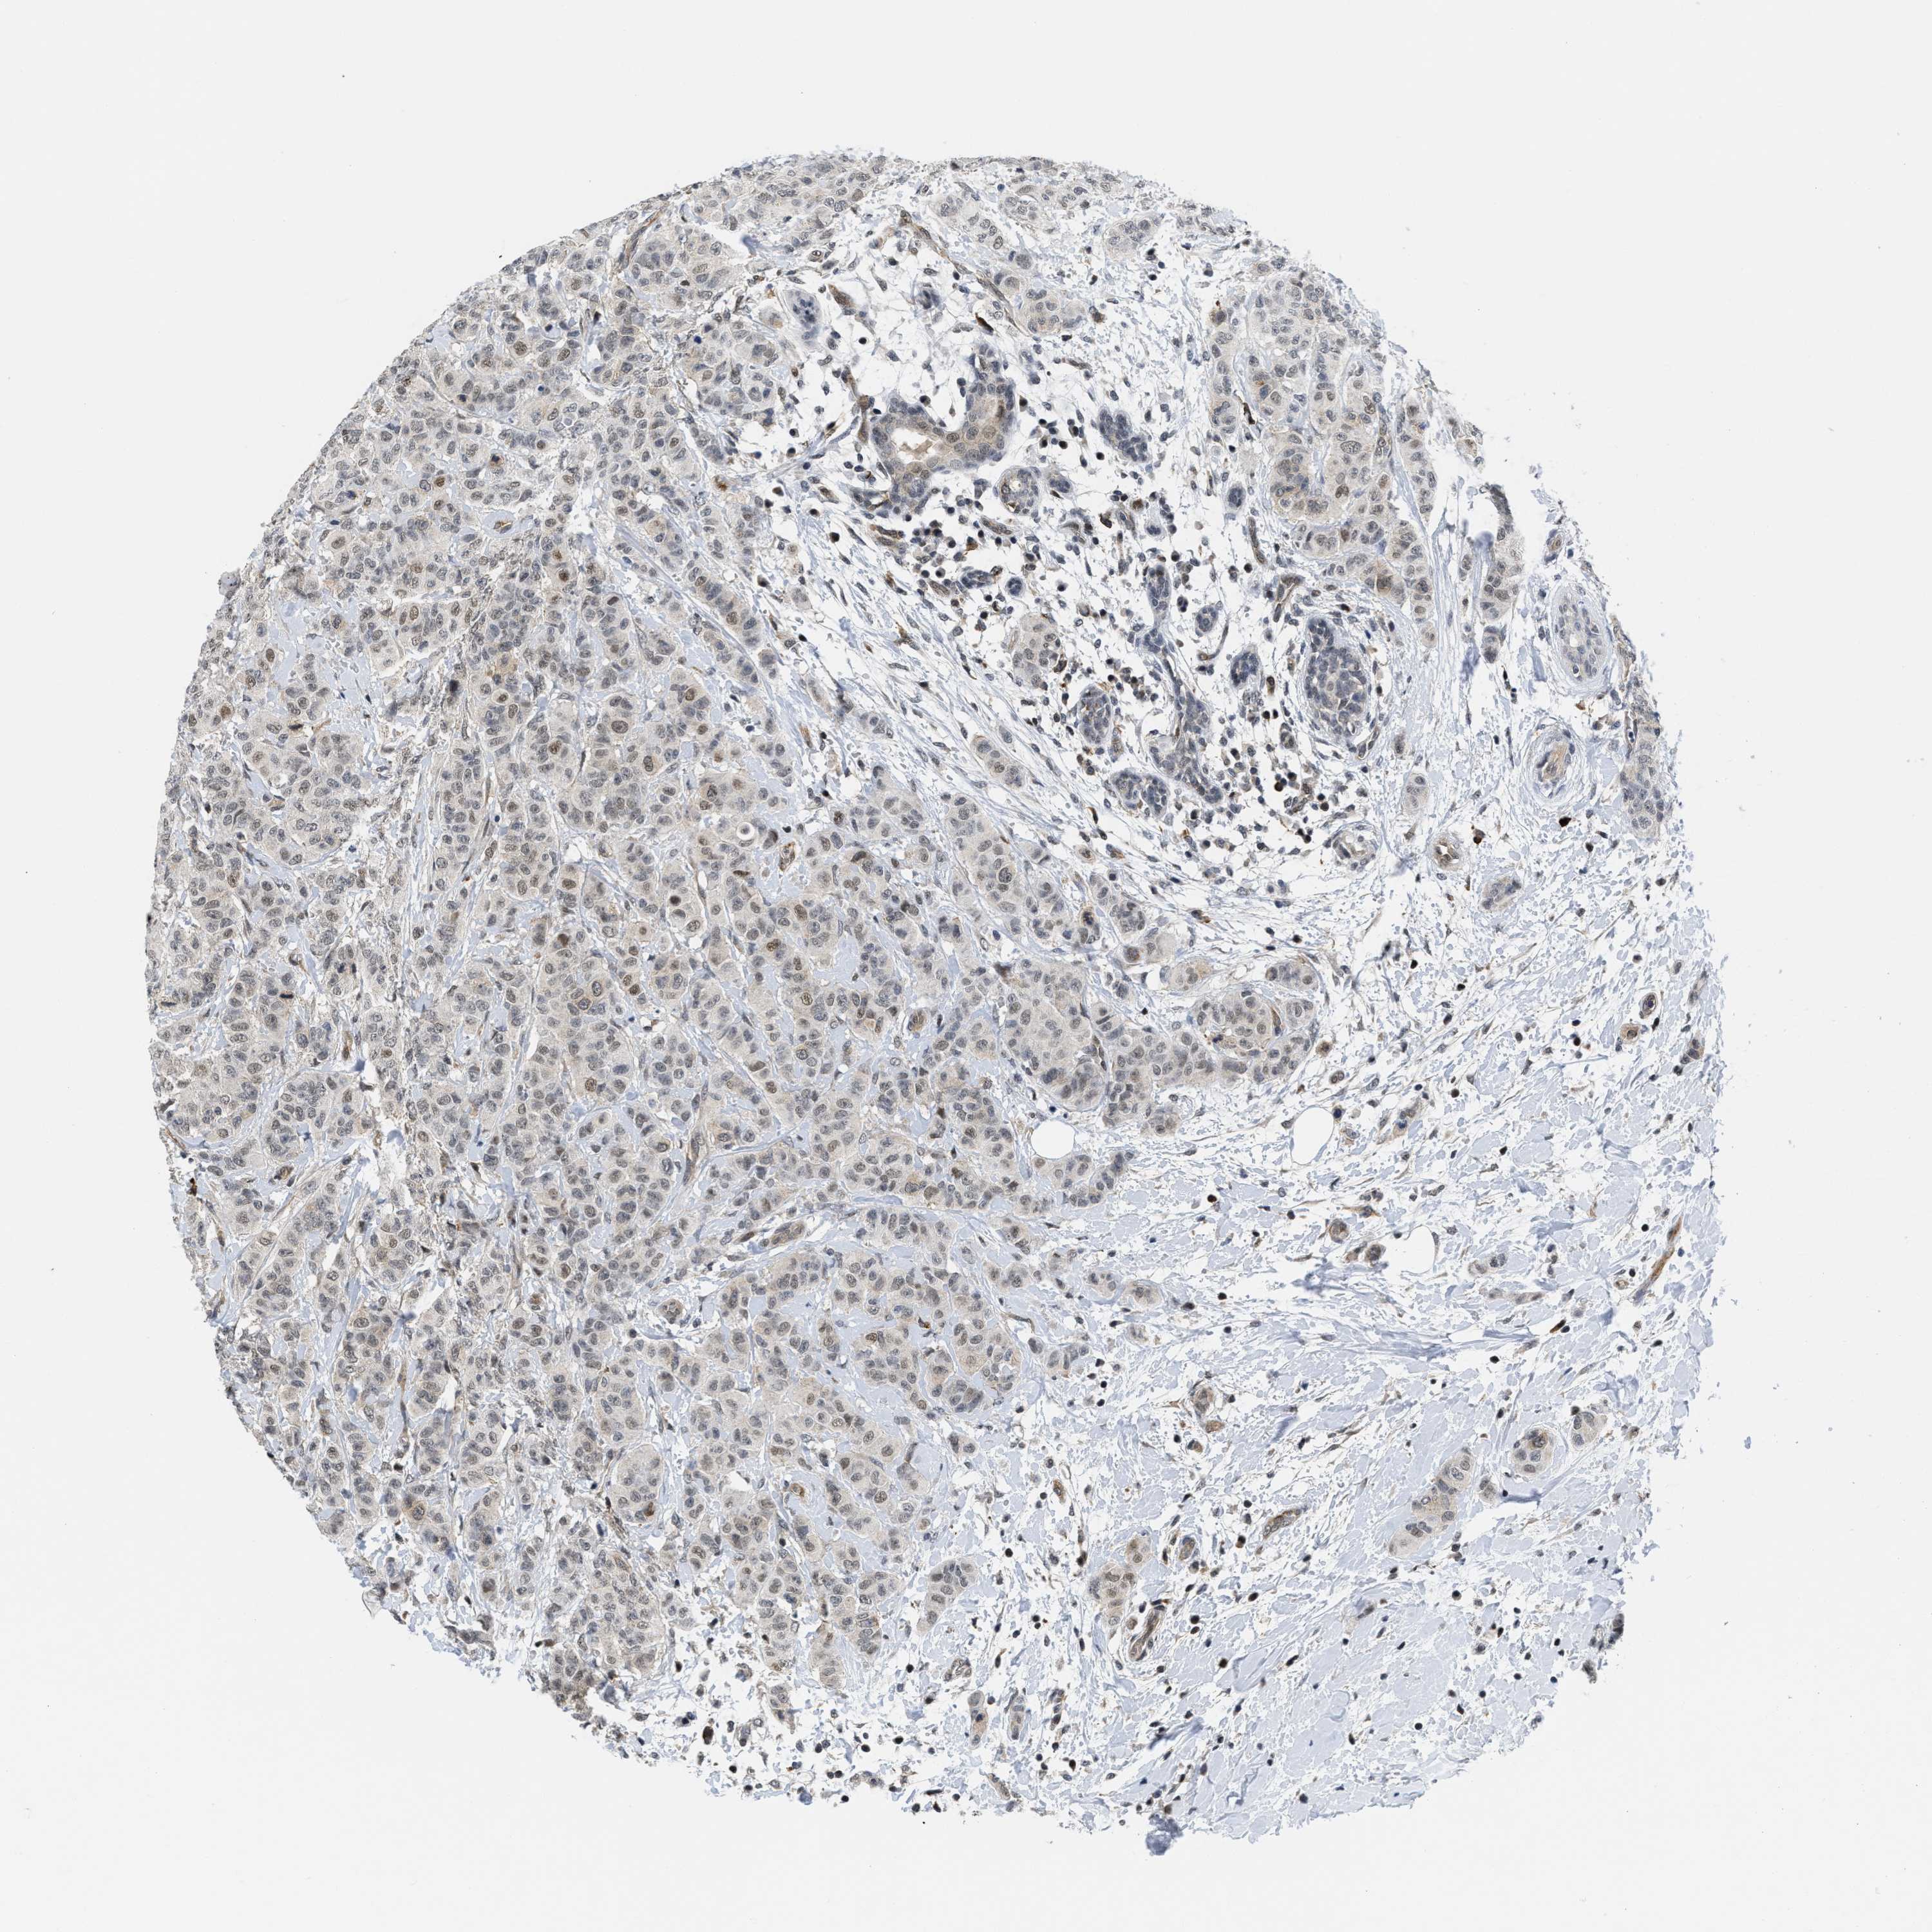

BRCA TCGA BRCA VALIDATION PROTEIN EXPRESSION